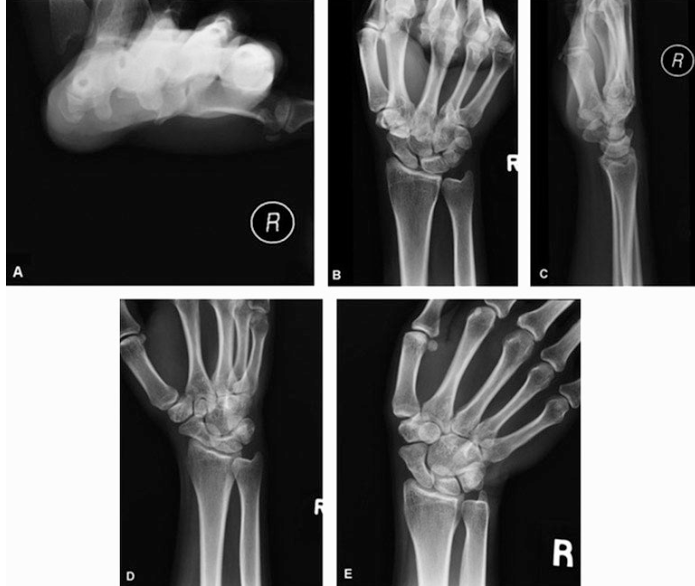

A 50-year-old, right-hand–dominant woman presents because of insidious onset, ulnar-sided wrist pain that has been present for the past 10 years. Ulnar impaction syndrome is suspected. Which of the following x-ray images shown is most appropriate for measurement of ulnar variance in this patient?

A) Carpal tunnel view

B) Clenched fist view

C) Lateral view

D) Oblique view

E) Ulnar deviated view

C. Lateral view

On lateral films, ulnar variance is measured between the most proximal point of the lunate fossa and the most distal articulation of the ulnar head, and studies have shown that this is the most accurate x-ray method of estimating ulnar variance.

Ulnar variance, or the relative difference in length of the ulna compared with the radius, has been implicated in a number of pathologic processes. Positive ulnar variance has been associated with tears of the triangular fibrocartilage complex and ulnar impaction syndrome. Negative ulnar variance has been associated with Kienböck disease and carpal instability.